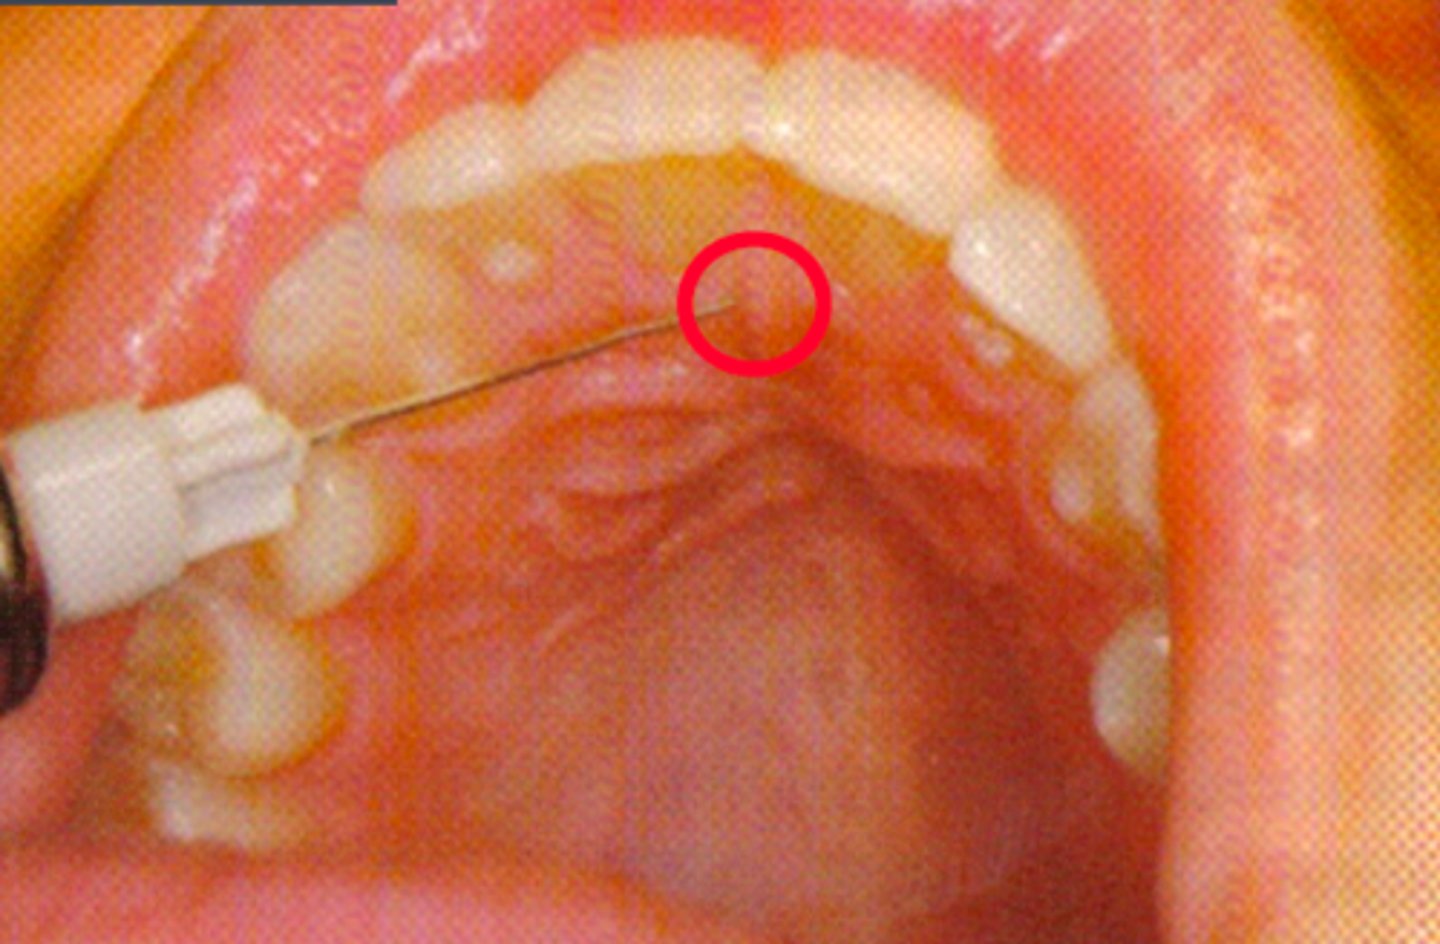

Nasopalatine Nerve Block (single injection)

ID the anesthesia technique:

Nasopalatine Nerve Block (multiple injections)

Incisive foramen on the anterior palate

what is the needle target for a Nasopalatine Nerve Block?

Palatal mucosa to the lateral border of the incisive papilla

what is the insertion point for a Nasopalatine Nerve Block (single injection technique)?

1st injection: labial frenum

2nd injection: interdental papilla between central incisors

3rd injection: incisive papilla (nasopalatine nerve block)

what is the insertion point for a Nasopalatine Nerve Block (multiple injection technique)?

Approach the injection site at a 45 degree angle toward the incisive papilla

what is the insertion path for a Nasopalatine Nerve Block?

3 to 5 mm

what is the depth for a Nasopalatine Nerve Block?

0.2 to 0.3 ml

what is the anesthetic volume for a Nasoalatine Nerve Block?

Nasopalatine Nerve Block (general)

This type of nerve block will result in the anesthesia of the palatal gingiva of the six anterior teeth and mucoperiosteum of the anterior third of the hard palate: